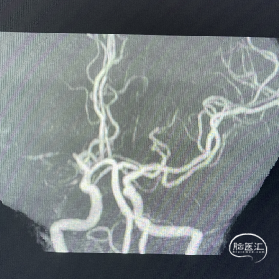

辅助检查:DWI:右侧大脑半球脑梗死灶;MRA检查:右侧大脑中动脉闭塞。

术前DSA影像:造影显示患者右侧大脑中动脉闭塞。